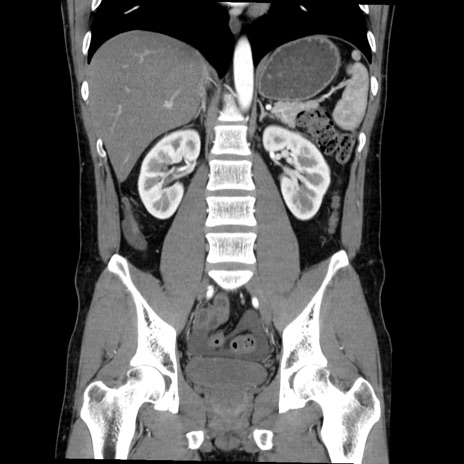

症例36(冠状断像)

【症例】20歳代 男性

【主訴】心窩部痛

【現病歴】今朝より上腹部痛あり。一旦軽快していたが再度出現したため救急要請。昨日夕に白身の魚を含む刺身を食べた。

【身体所見】BP 136/89mmHg、HR 74/min、BT 37.0℃、腹部:膨満、軟、心窩部に圧痛あり。反跳痛なし、筋性防御なし、腸雑音やや亢進あり。

【データ】WBC 17700、CRP 0.48